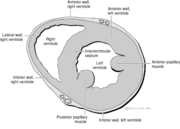

| 12:50, 26 April 2009 | AP4CH.svg (file) |  |

38 KB | April | 1 | |